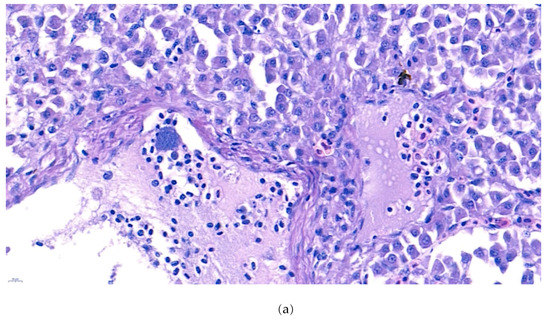

The internal lesions of the moribund fish were concentrated on the liver and kidney. Therefore, the spleen, kidney, and liver of five diseased fish were histopathologically analyzed. Significant tubular degeneration (Figure 2) and hyaline droplet accumulation in tubular epithelium (Figure 3) was observed in the infected posterior kidneys.

Figure 2.

(a). Representative image of hematoxylin and eosin-stained tissue section showing degenerated tubules surrounded by lymphocytes and macrophages in the kidney of the diseased fish. Signs of phagocytized rod-shaped bacterium and cellular debris can also be observed. (arrow: phagocytized rod-shaped bacterium, arrow head: cellular debris) (b). Negative fish group kidney image stained with hematoxylin and eosin. (Bar indicating 10 µm).

Furthermore, the infiltration of diverse immunocytes, including lymphocytes and macrophages, was observed surrounding the tubule (Figure 2). In addition, signs of bacteremia along the degenerated tubule (Figure 3) were observed with cellular debris surrounding the tubules (Figure 2). Similar signs were also observed in the liver of the diseased fish. A few necrotizing areas with infiltration of macrophages and lymphocytes and vacuolation of hepatic cells was observed (Figure 4a,b).